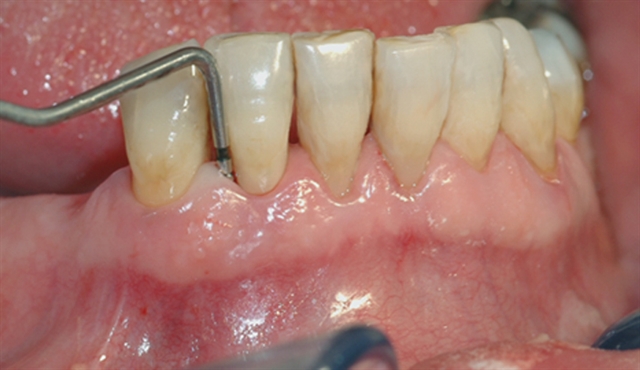

• Instrumentet er her lagt utanpå tannkjøtet for å vise kor omfattande festetapet er.

• Beintapet vert bekrefta av eit røntgenbilete – skaden er så stor at tanna må fjernast.